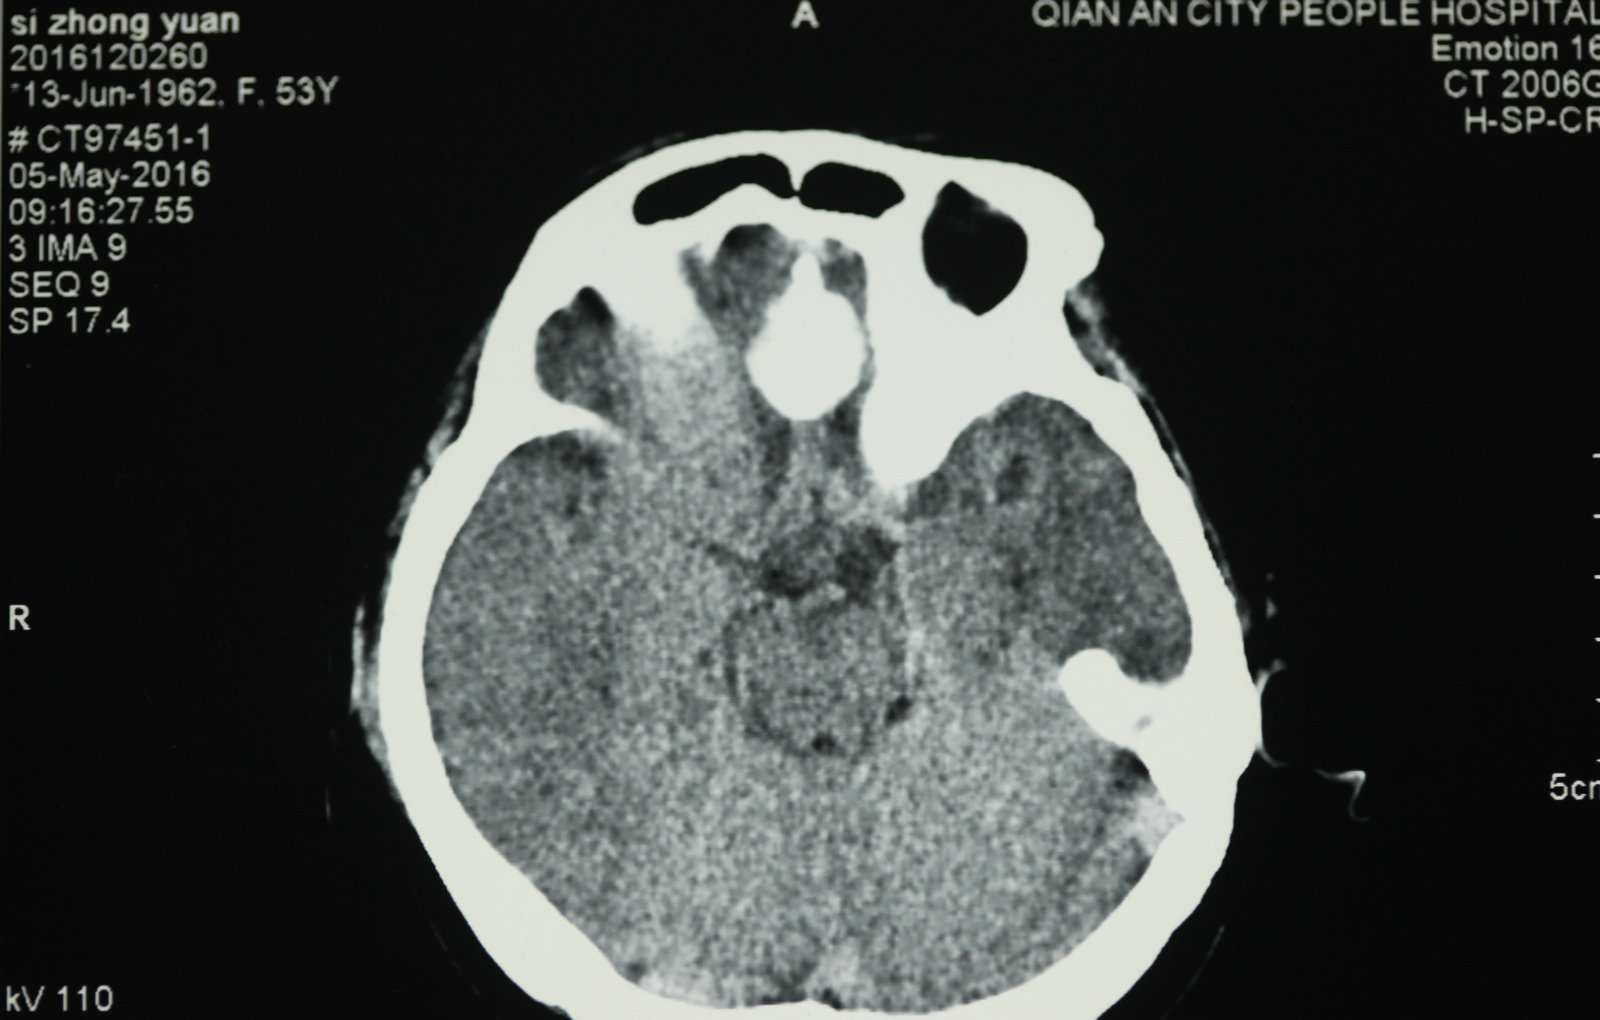

显微神经外科学是以应用手术显微镜为标志,但是,我们决不能片面的将显微神经外科学理解为只要手术中使用手术显微镜就是显微神经外科手术。而显微神经外科学的正确概念,足指以近代影像学为诊断基础,一整套与显微手术相匹配的手术设备、显微神经外科手术器械为保证的,以颅内病灶为中心的手术。显微神经外科学不仅是技术,更重要的是概念的更新。

将手术显微镜和显微神经解剖结合,会使许多常规的神经外科手术得到进一步完善,如脊髓的切除、动脉瘤的夹闭等,并开创了以往神经外科医生不能施行的手术。因为对显微神经解剖认识的深入,医生能够以较小的脑牵开或皮层结构切开,经过神经血管间隙,安全准确地达到脑深部病灶,进行微损伤的手术切除。总之,显微神经解剖和显微外科技术结合,可在微创下切除以往不能手术切除的病变。而应用手术显微镜进行神经外科解剖研究和神经外科教学是对以往的肉眼神经解剖研究的全新修正,它使肉眼观测困难的微小结构和纤细神经清晰可辨,属于全新的领域。 手术显微镜的应用又使医生感到手术操作在灵活性和精确性方面受限,因此又有学者开始探索机器人辅助手术,这将开创精细外科技术的新境界,当然它也要求有新的显微解剖知识与其适应。其他新技术的发展也需要以精确的显微神经解剖知识为基础,如在血管内栓塞治疗动脉瘤时,需要详尽了解载瘤动脉、穿通动脉及其解剖变异经过缜密的开颅设计,可达到颅底任何部位。将显微神经外科解剖研究结合影像学定位,利用脑表面的沟裂建立细小孔道,一些脑深部解剖能理想的显露。显微解剖研究也研究了一些新的手术入路,如经脉络膜入第三脑室手术入路、经鼻腔入蝶窦的垂体瘤手术入路等。在未来,通过更深入的显微外科解剖学研究,还会有一些新的更好的手术入路研究出来。另外一些新的手术技术的改进和完善也需要对显微外科解剖的深入理解。 随着神经精细结构显露技术的显著提高,显微解剖照片准确鲜明,生动活泼,非常优美,适合于神经外科学习和参考。